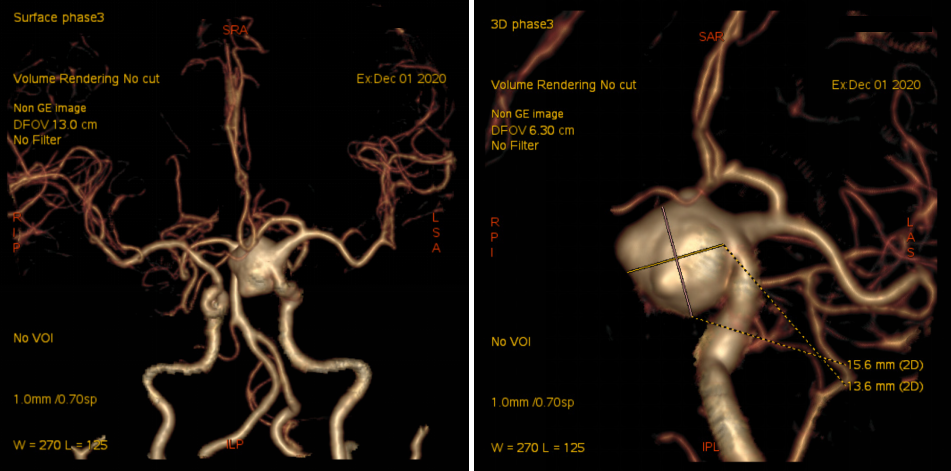

入院后予完善头颅DSA检查提示左侧颈内动脉眼动脉段动脉瘤;头颅MR提示脑内多发陈旧梗死,告知其介入栓塞、开颅夹闭等治疗方式、利弊、风险及费用等,患方商量后决定行开颅动脉瘤夹闭术。

头颈部CTA

术前DSA